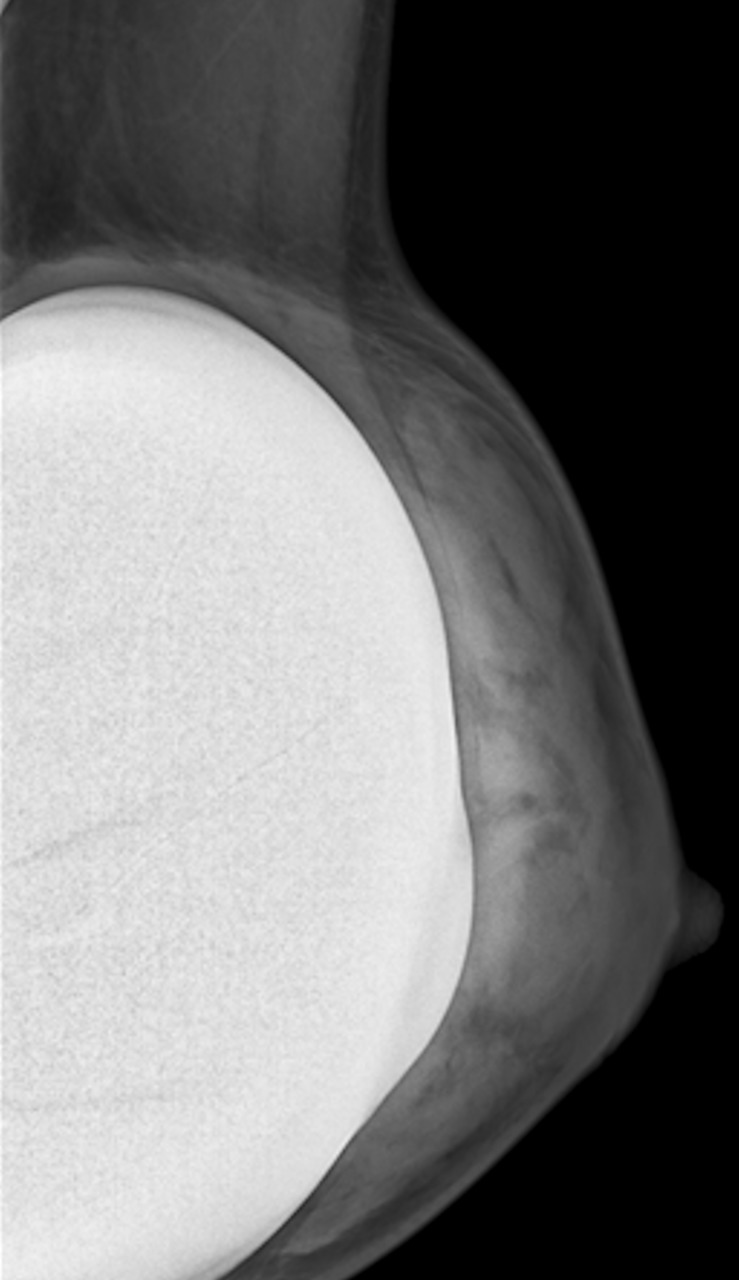

En mammographie : aspect rond, régulier, hyperdense si en silicone (fig. 1), moins dense en cas de sérum physiologique (fig. 2). Confirmé par la tomosynthèse (3D), à utiliser avec parcimonie en raison de l’exposition aux rayons.

• extracapsulaire (fig. 3 et 4), contenu hétérogène avec échos internes et perte du contour régulier de la paroi à l’échographie. Diagnostic confirmé par l’IRM mammaire avec séquences dédiées silicone, qui montre l’incontinence de la prothèse (paroi irrégulière) et des dépôts de silicone rétro- ou périprothétiques. Des ganglions chargés en silicone peuvent être visibles.